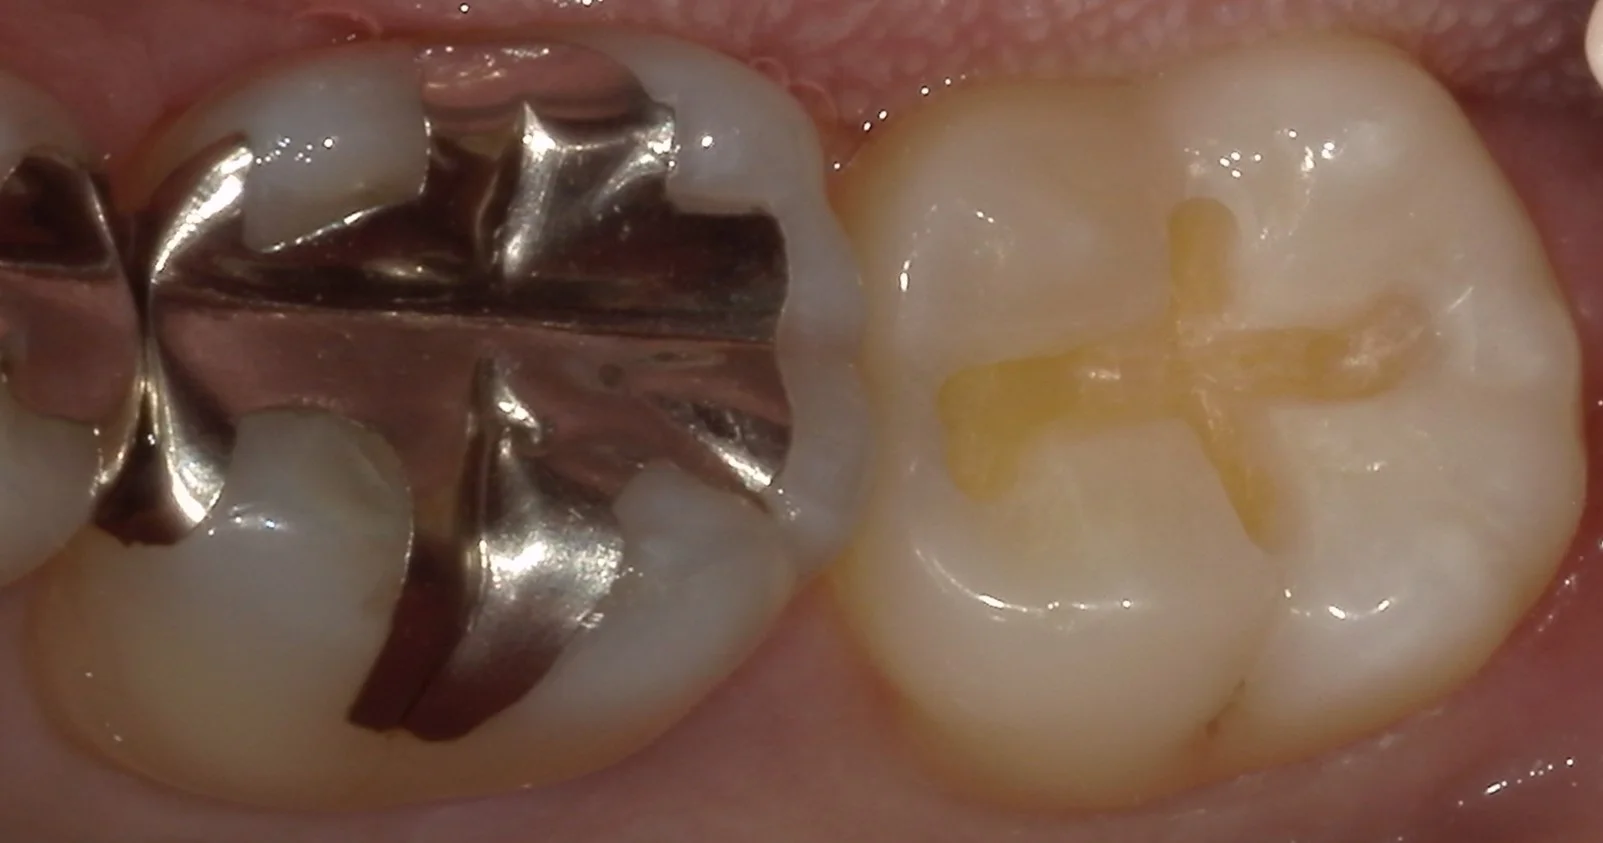

そして、虫歯を取り切ったのがこちらの写真です。

綺麗に歯の色が出たのがわかるかと思います。

詰め物の治療をする際、着色部分も含めてしっかりと除去しておいた方が接着には有利に働くのがわかっていますので、無理のない範囲で除去しきるようにしています。